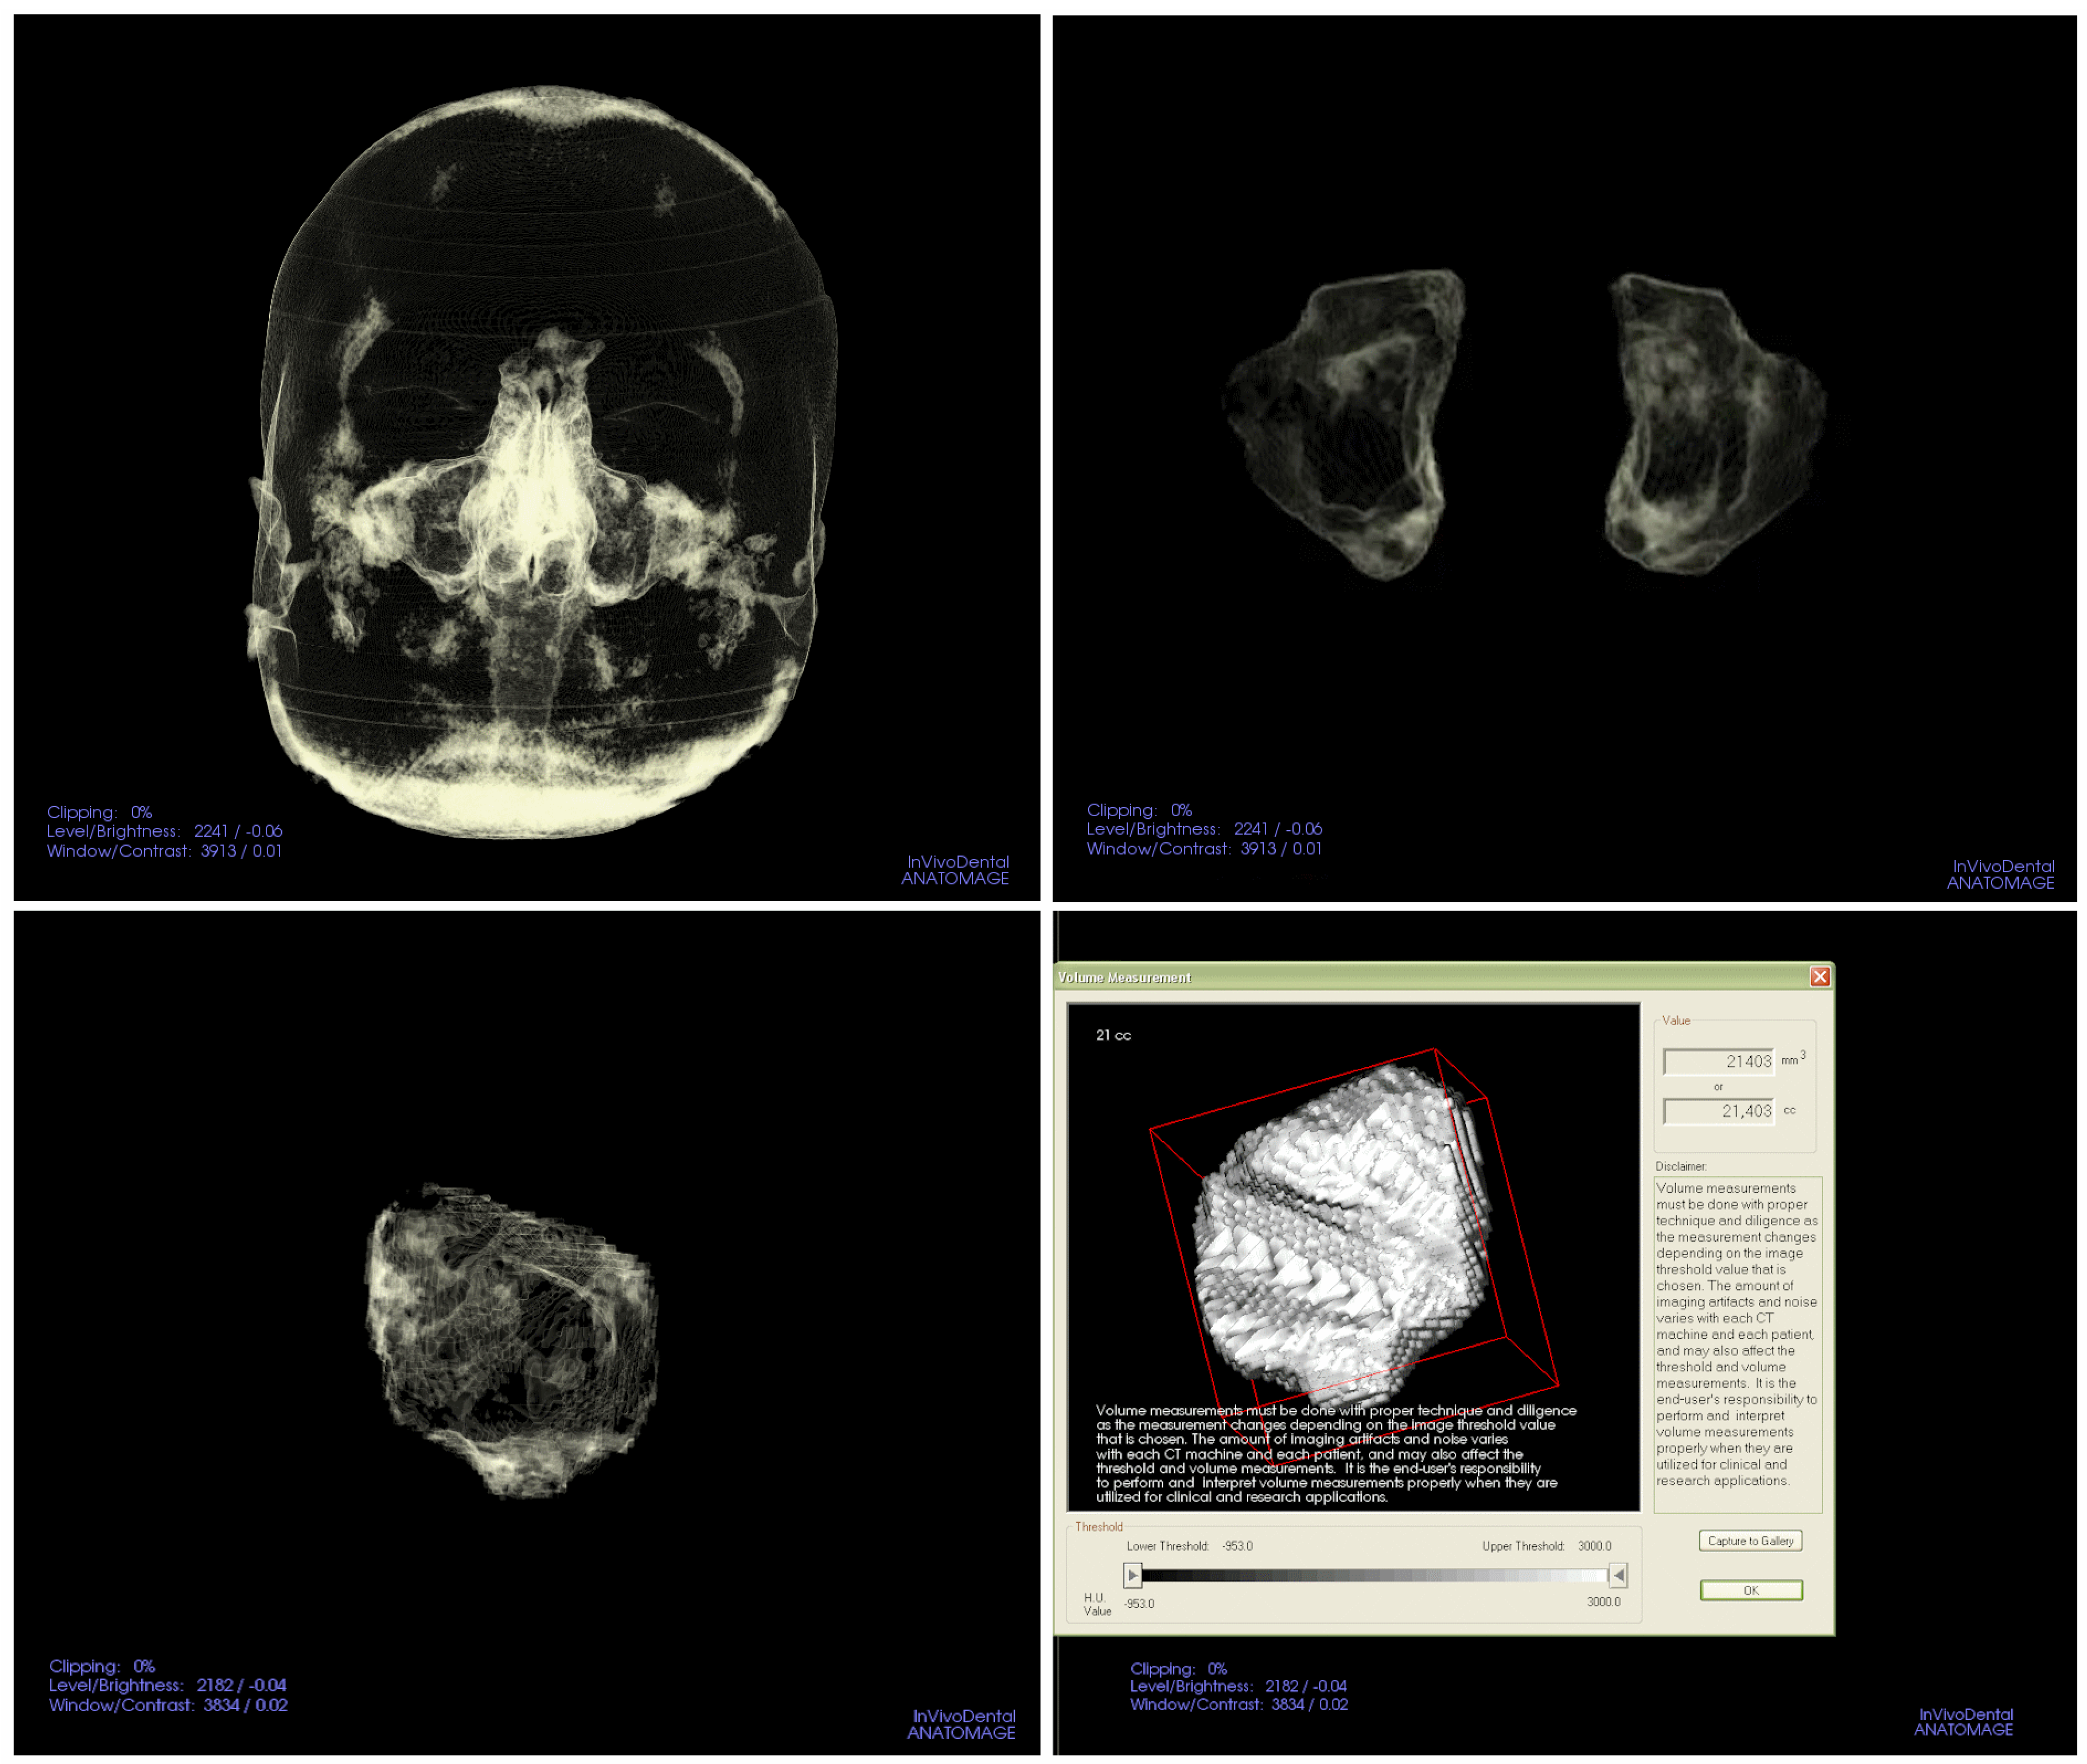

2. Materials and Methods